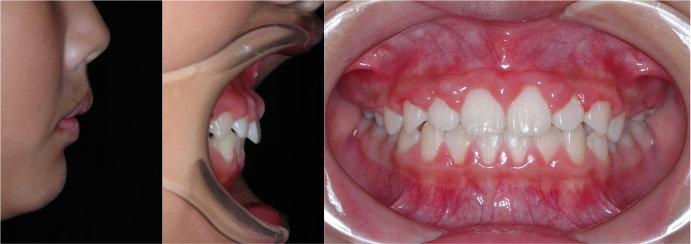

| Case2 |

| 出っ歯 |

| <治療前> |

| <治療後> |

| 主訴 |

上の前歯が出ている |

| 診断名 |

上顎前突 |

| 年齢 |

8歳 |

| 使用装置 |

マルチブラケット装置/ヘッドギア |

| 抜歯部位 |

永久歯の抜歯は無し |

| 治療期間 |

3年6か月 |

| 治療費概算 |

検査・診断料:5万円+税 装置・技術料:25万円+税 来院ごとの処置・管理料:5,000円+税 保定装置料:5万円+税 |

| リスク・副作用 |

特になし |